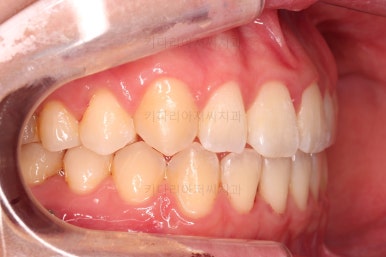

아래 앞니도 단순히 머리 부분만 뒤로 눕힌 것이 아니라 뿌리까지 뒤로 당겨왔고요.

6. 전후 사진 비교

교합, 가지런함, 앞니 각도 모두 좋아졌습니다.

얼굴 모습에서의 변화도 웃을 때 앞니의 느낌, 웃을 때 보이는 앞니의 각도, 아랫입술의 변화 등 모든 면에서 다 좋아진 치료였습니다.